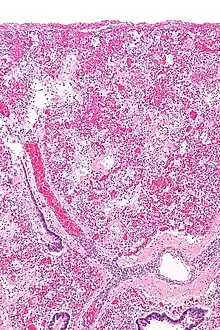

ARDS is a form of fluid accumulation in the lungs not explained by heart failure (noncardiogenic pulmonary edema). It is typically provoked by an acute injury to the lungs that results in flooding of the lungs' microscopic air sacs responsible for the exchange of gases such as oxygen and carbon dioxide with capillaries in the lungs.[13] Additional common findings in ARDS include partial collapse of the alveoli(atelectasis) and low levels of oxygen in the blood (hypoxemia). The clinical syndrome is associated with pathological findings including pneumonia, eosinophilic pneumonia, cryptogenic organizing pneumonia, acute fibrinous organizing pneumonia, and diffuse alveolar damage (DAD). Of these, the pathology most commonly associated with ARDS is DAD, which is characterized by a diffuse inflammation of lung tissue. The triggering insult to the tissue usually results in an initial release of chemical signals and other inflammatory mediators secreted by local epithelial and endothelial cells.

Neutrophils and some T-lymphocytes quickly migrate into the inflamed lung tissue and contribute in the amplification of the phenomenon. The typical histological presentation involves diffuse alveolar damage and hyaline membrane formation in alveolar walls. Although the triggering mechanisms are not completely understood, recent research has examined the role of inflammation and mechanical stress.